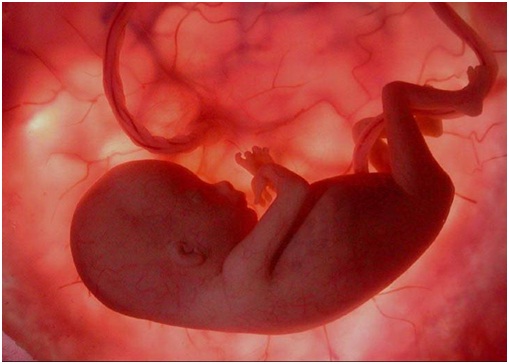

متى تشعرين بحركة الجنين؟

تبدأ حركة الجنين في الشهر الرابع. وعادة ما تشعر بها بشكل أوضح الأم النحيفة أو الأم التي مرت بتجربة الحمل من قبل، في بعض الأحيان لا يمكن تمييز تلك الحركة، وتظنها الأم مجرد قرصة جوع أو تشنجات عضلية.

كيف تكون حركة الجنين؟

البعض يصفونها كأنها فرقعات الفشار أو ضربات أجنحة الفراشات أو خبطات سمكة زينة في الماء. ولكن مع تكرار الحركة بشكل مستمر سوف تتمكني من تمييزها عن أية حركة أخرى داخل جسمك.

في البداية سوف تكون قليلة وعلى فترات متباعدة، ومع مرور الوقت سوف تشعرين بزيادة الحركات مع نمو الجنين ونمو عضلاته.

في هذه المرحلة ينمو الجنين بسرعة فلا تتوقعين أن تشعري بأي حركة جنينية، الجنين في هذه المرحلة صغير جداً على أن تشعري به.

في الأسبوع السادس عشر، قد تشعر الأمهات النحيفات وهؤلاء اللائي مررن بتجربة الحمل فيما سبق، ببعض حركات الجنين، أغلب النساء لن يلاحظن تلك الحركة قبل عدة أسابيع أخرى، مع حلول الشهر الخامس، تشعرين بحركات الجنين وهي لا تزال بسيطة ولكنها تزداد يوما عن يوم، سوف تشعرين بحركات بهلوانية بعض الأحيان وبركلات في أحيان أخرى (بعضها ضعيف وبعضها قوي) وذلك مع تطور جهاز الجنين الحركي وزيادة قوة عضلاته، إن لم تشعري بحركة في الشهر الخامس عليك باستشارة الطبيب والاطمئنان على الجنين.

مع مرور الوقت ونمو الجنين أكثر وأكثر، سوف يضيق عليه الرحم أكثر وأكثر، ولكنك سوف تشعرين بحركته باستمرار.